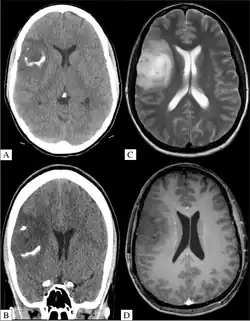

Bildgebung

Typischerweise erfolgt die Diagnostik durch eine Magnetresonanztomographie mit und ohne Kontrastmittelgabe oder durch eine Computertomografie (CT). Eine Kontrastmittelanreicherung zeigt nicht so sicher wie bei Astrozytomen einen Übergang zur Anaplasie an.

Die meisten Oligodendrogliome zeigen Verkalkungen, bei Grad 3 sind diese fast immer vorhanden.[5]